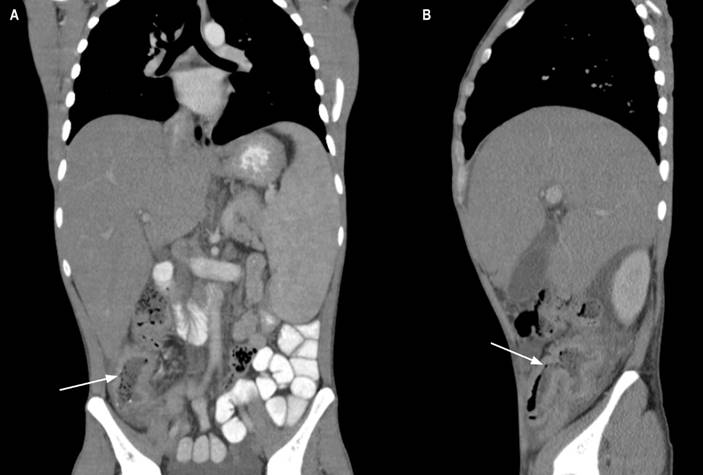

Se consideró una clínica de neoplasia gastrointestinal teniendo en cuenta el antecedente familiar, se solicitó una tomografía de abdomen con contraste en el que se identificó un engrosamiento concéntrico de la pared del colon ascendente con leve realce, múltiples adenopatías mesentéricas y retroperitoneales (Figura 1). En los paraclínicos solicitados al ingreso se documentó anemia normocítica normocrómica, linfopenia, trombocitopenia leve, elevación de fosfatasa alcalina e hipoalbuminemia.

Figura 1 Tomografía computada de abdomen con contraste corte coronal y sagital. A. Engrosamiento concéntrico de la pared del colon ascendente con leve realce (flecha). B. Engrosamiento del íleon distal y válvula ileocecal (flecha). Fuente: historia clínica del paciente.